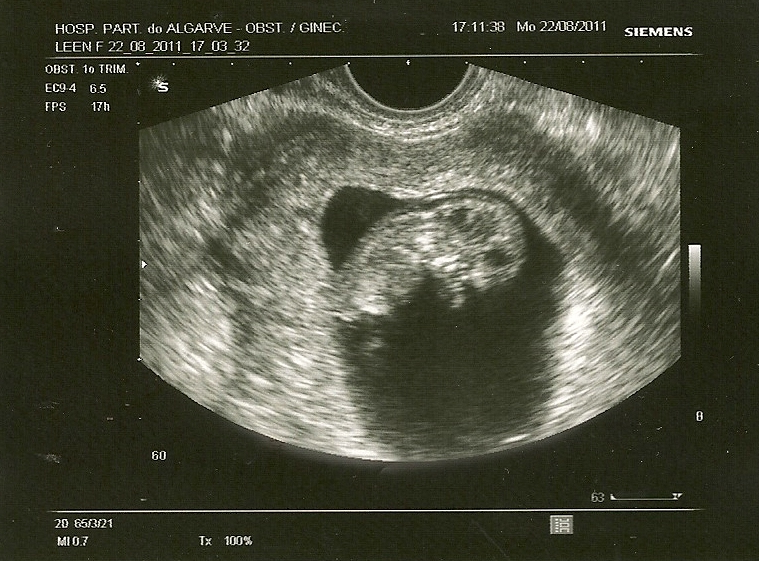

Vandaag was het dan eindelijk zo ver!! We zijn onze kleine BIB (baby in buik) gaan bewonderen en onze dag kon niet meer stuk. Is nu bijna 3,5cm en ben 3 dagen vooruit gezet. Dus vandaag 10 weken 2 dagen. Weer een stukje dichter bij de 12 weken. We hebben het hartje gehoord. Boenke boenke boenke, zo speciaal toch weer zeg!! Kon het weer niet droog houden. Emo kip dat ik ben haha!

Echo: 10 w 2 d